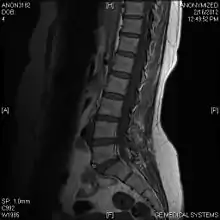

Limbus vertebra

A limbus vertebra is a bone tubercle formed by bone trauma on a vertebral body, bearing a radiographic similarity to a vertebral fracture. The anterior-superior corner of a single vertebra is the common site for this defect although it can also be seen at the inferior corner as well as the posterior or anterior margin. Anatomically, it is assumed to be an intra-vertebral body herniation of the disc material occurring during adolescent growth spurt when the ring apophysis has not yet fused. It was first described by Schmorl in 1927 and later in detail by Leif Sward and Adad Baranto.

Viewed in a lateral radiograph, it appears as a triangular shaped bone fragment, not unlike an anterior lip fracture, but with softer edges.

Limbus vertebra is not always symptomatic, but severe cases may lead to more serious pathological conditions and chronic pain. In rare instances, a posterior limbus vertebra has been described causing radiculopathy due to nerve root compression.